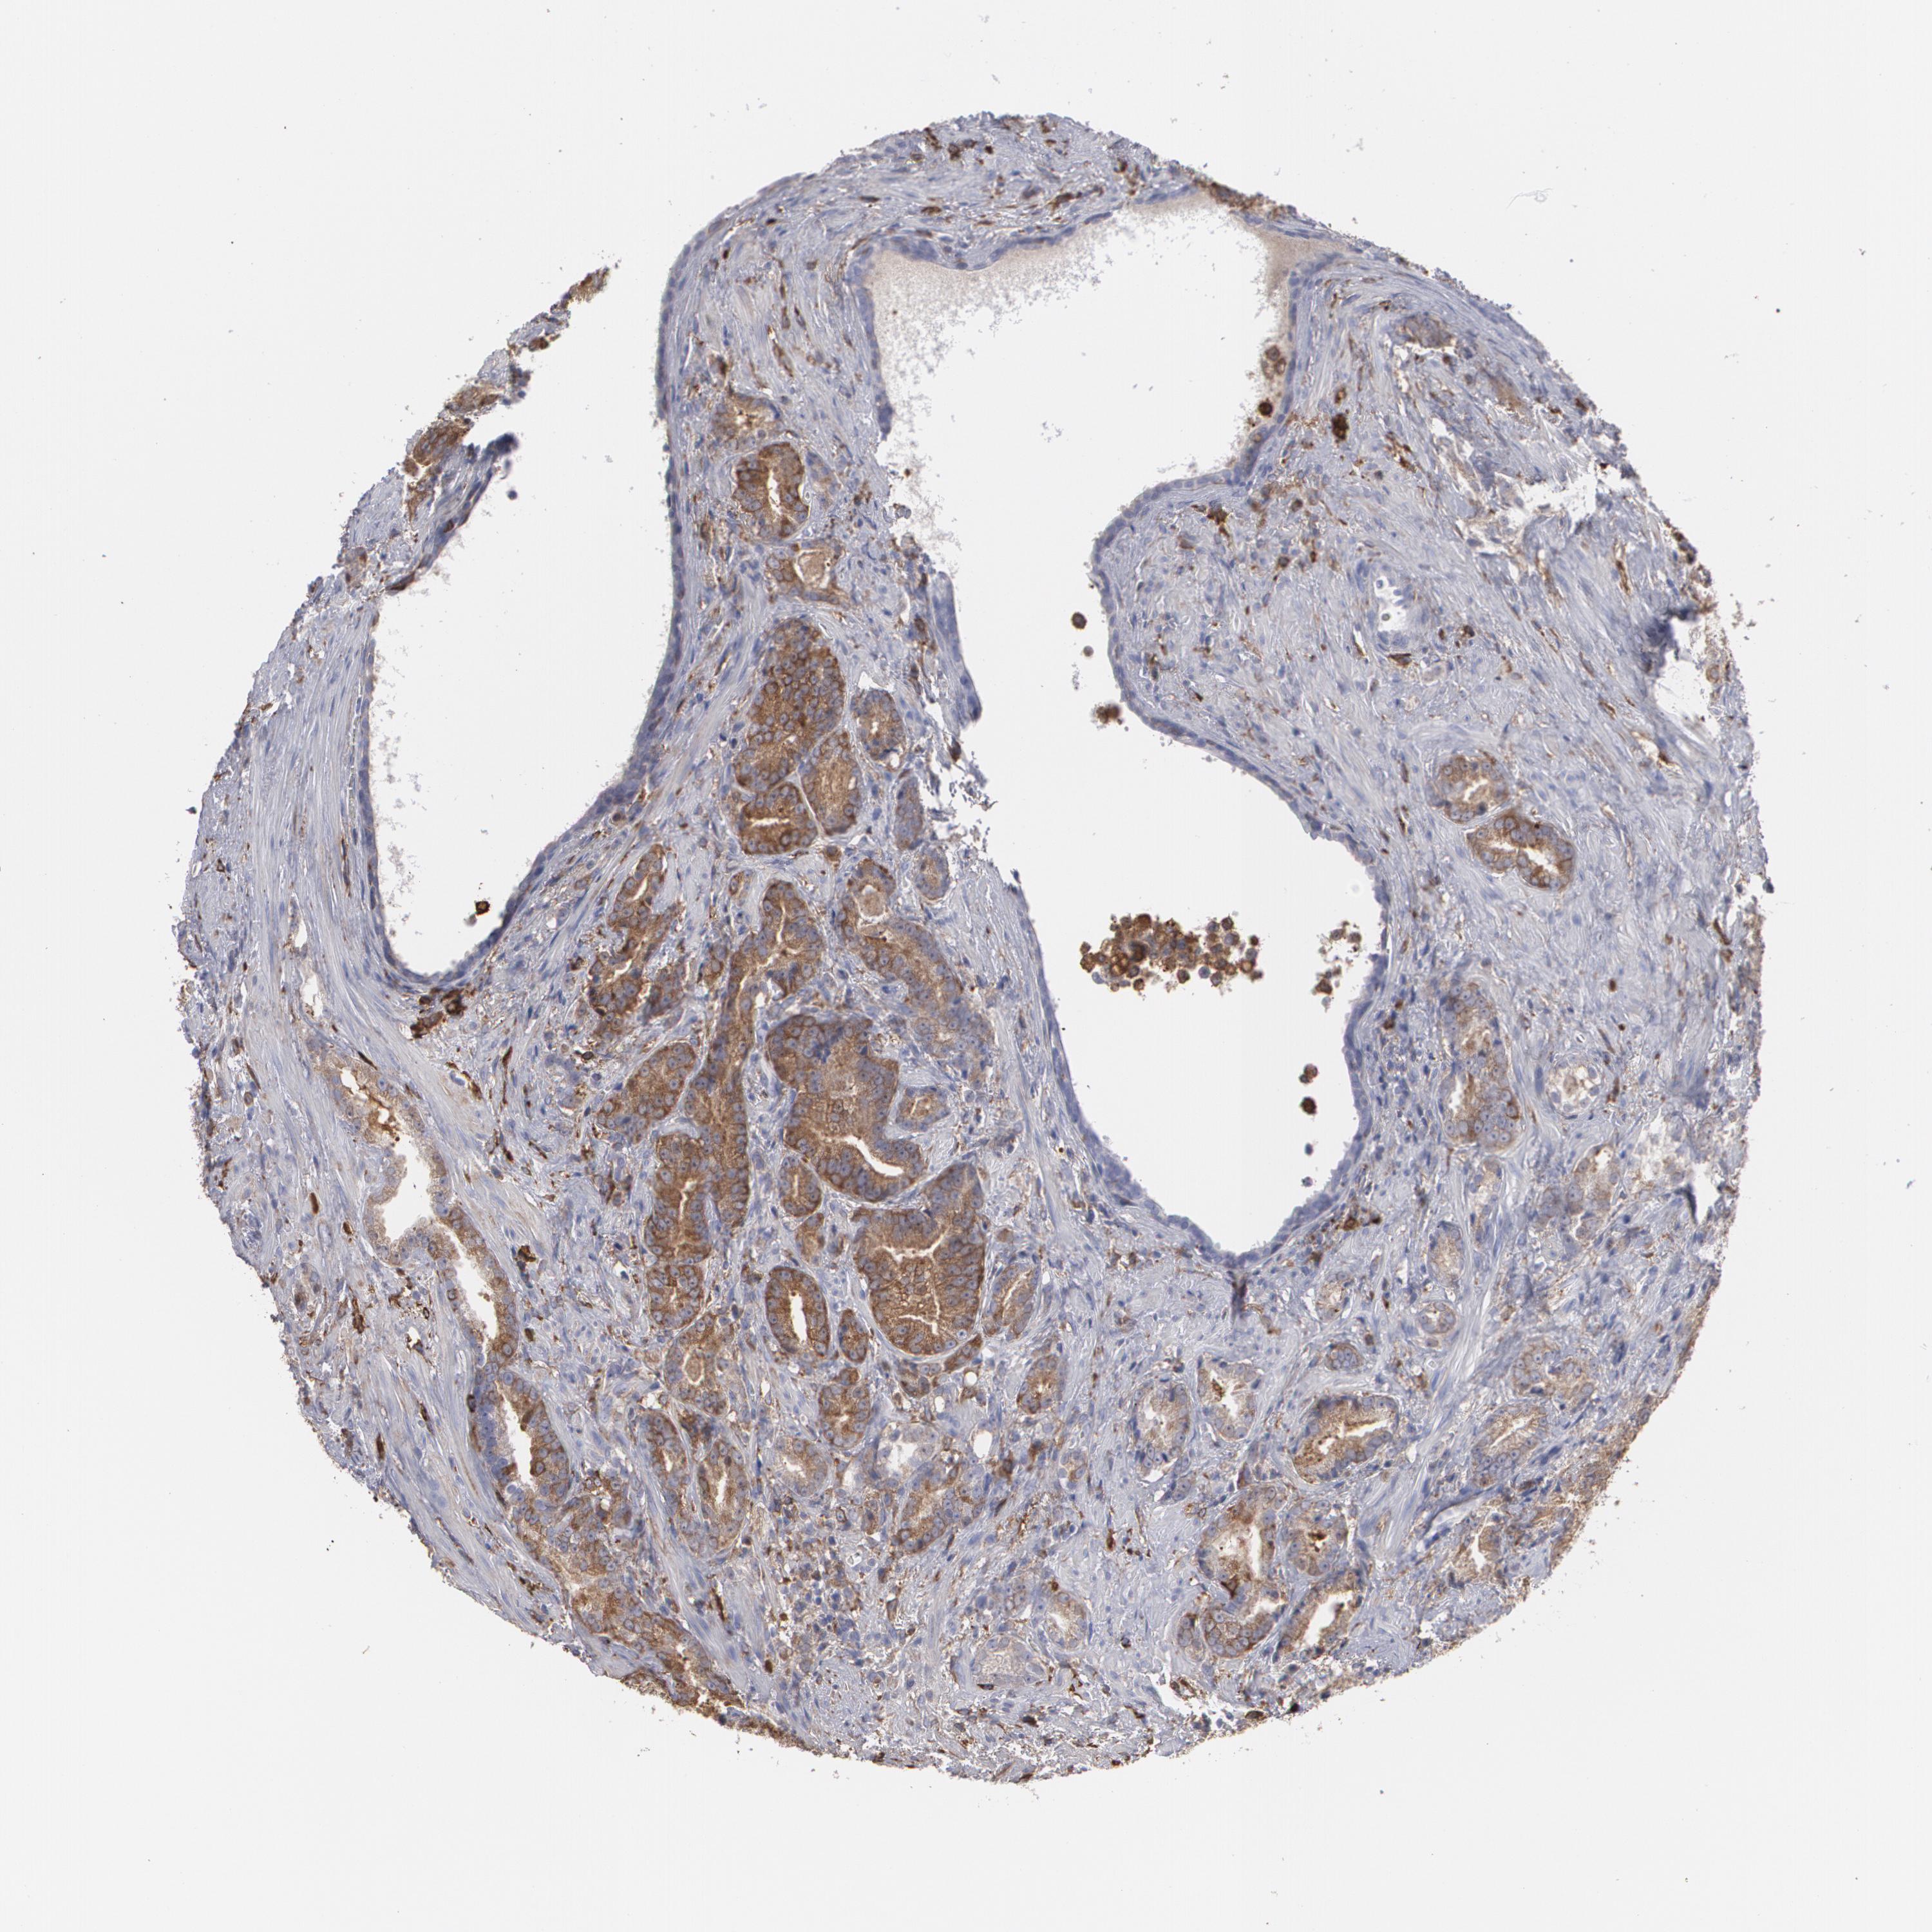

PROSTATE CANCER - Protein expressioni

A mouse-over function shows sample information and annotation data. Click on an image to view it in a full screen mode. Samples can be filtered based on level of antibody staining by selecting one or several of the following categories: high, medium, low and not detected. The assay and annotation is described here.

Antibody stainingi

Antibody staining in the annotated cell types in the current human tissue is reported as not detected, low, medium, or high, based on conventional immunohistochemistry profiling in selected tissues. This score is based on the combination of the staining intensity and fraction of stained cells.

Each image is clickable and will lead to virtual microscopy that enables deeper exploration of all samples and also displays staining intensity scores, fraction scores and subcellular localization as well as patient and tissue information for each sample.

Antibody HPA001536

Antibody CAB035996

Staining

High

Medium

Low

Not detected

Intensity

Strong

Moderate

Weak

Negative

Quantity

>75%

75%-25%

<25%

None

Location

Nuclear

Cytoplasmic/membranous

Cytoplasmic/membranous,nuclear

Adenocarcinoma, Medium grade

Adenocarcinoma, High grade

Adenocarcinoma, Low grade